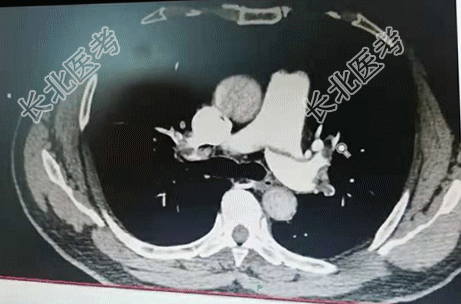

【现病史】2天前,患者无明显诱因出现右侧胸痛不适感,伴呼吸费力。当时无咳嗽、咳痰、发热等症状。以为是劳累导致的症状,经休息后症状缓解不明显,今晨起疼痛症状加重,家属拨打120急救送入我院,急诊科查指脉氧98%,行肺部CTA检查时指脉氧降至92%,肺部CTA显示:肺栓塞。诊断为:肺栓塞。发病以来饮食、睡眠差、小便正常,大便未解,体重无明显变化。

【辅助检查】肺部CTA显示:肺栓塞。心电图:标3、Avf、V₄-V₆导联T波改变。